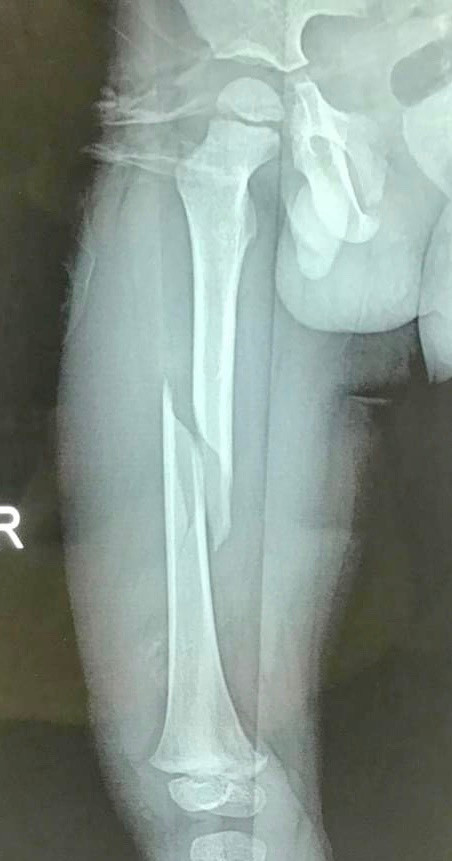

![]() |

| Phần xương đùi bị gãy của bệnh nhi. Ảnh: Bệnh viện Hữu Nghị |

Trao đổi với PV VietTimes, BS. Trần Cửu Long Giang – Trưởng Khoa ngoại Thần kinh - Chấn thương Chỉnh hình, Bệnh viện Hữu Nghị - cho biết: Bệnh nhi nhập viện do tai nạn cột bê tông đè vào chân. Đây là một thương tổn nặng khiến bé bị gãy chéo vát thân xương đùi phải – một xương dài lớn nhất trong cơ thể, gây ra tình trạng mất máu nhiều. Ngoài ra phần mềm cân cơ bao quanh xương còn bị đụng dập nhiều. Mặc dù bé đã được nắn chỉnh bó bột nhưng kết quả không như mong đợi.

Các bác sĩ tại Khoa Ngoại Thần kinh - Chấn thương chỉnh hình, Bệnh viện Hữu Nghị đánh giá đây là trường hợp gãy chéo vát, di lệch nhiều, rất khó năng chỉnh bằng phương pháp bó bột.